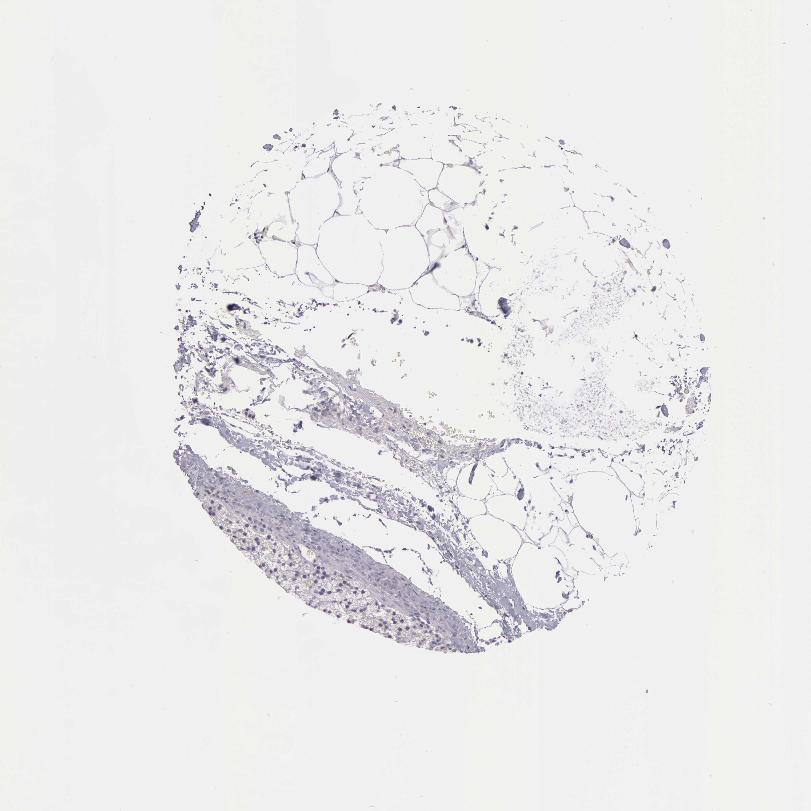

TISSUE PRIMARY DATA ADRENAL GLAND Show tissue menu

ADRENAL GLAND - Antibody stainingi

Antibody staining in the annotated cell types in the current human tissue is reported as not detected, low, medium, or high, based on conventional immunohistochemistry profiling in selected tissues. This score is based on the combination of the staining intensity and fraction of stained cells.

Each image is clickable and will lead to virtual microscopy that enables deeper exploration of all samples and also displays staining intensity scores, fraction scores and subcellular localization as well as patient and tissue information for each sample.

Antibody HPA019527Antibody HPA020912Antibody CAB001809

Glandular cells MediumLowNot detected